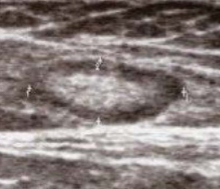

This pseudo-micronodular appearance of the thyroid is characteristic of:

Hashimoto’s thyroiditis

Which statement about the sonographic appearance of Hashimoto’s thyroiditis is TRUE?

It shows hypoechoic micronodules with echogenic septations, creating a pseudonodular or “giraffe” pattern, and Doppler may show normal, decreased, or occasionally increased flow.